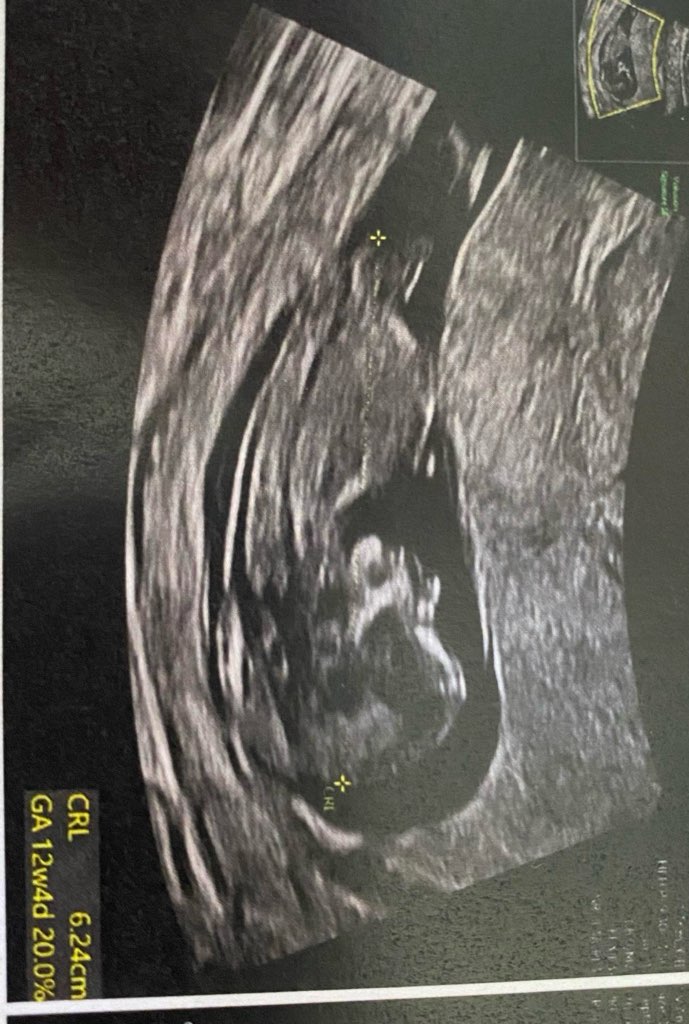

Zaczynam właśnie 7 miesiąc ciazy, czas kompletować wyprawkę :) na 1 prenatalnych i wizytach lekarskich do 19 tyg chłopak, widziałam siusiaka, w 20 tyg na 70% dziewczynka, później już nic nie było widać… ostatnie USG, ułożenie miednicowe, pępowina między nogami :p czy na tych zdjęciach da się coś rozpoznać względem wyrostka? :)